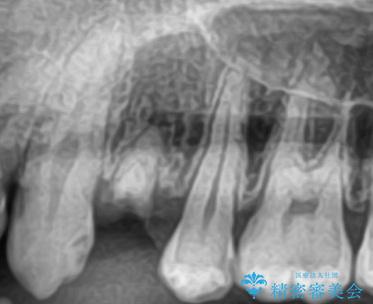

長い間虫歯を放置していたため、根っこだけになっている状態でした。このままでは被せ物を被せられないため抜歯を行い治癒を待った後にインプラントを埋入しオールセラミッククラウンで治療を行いました。